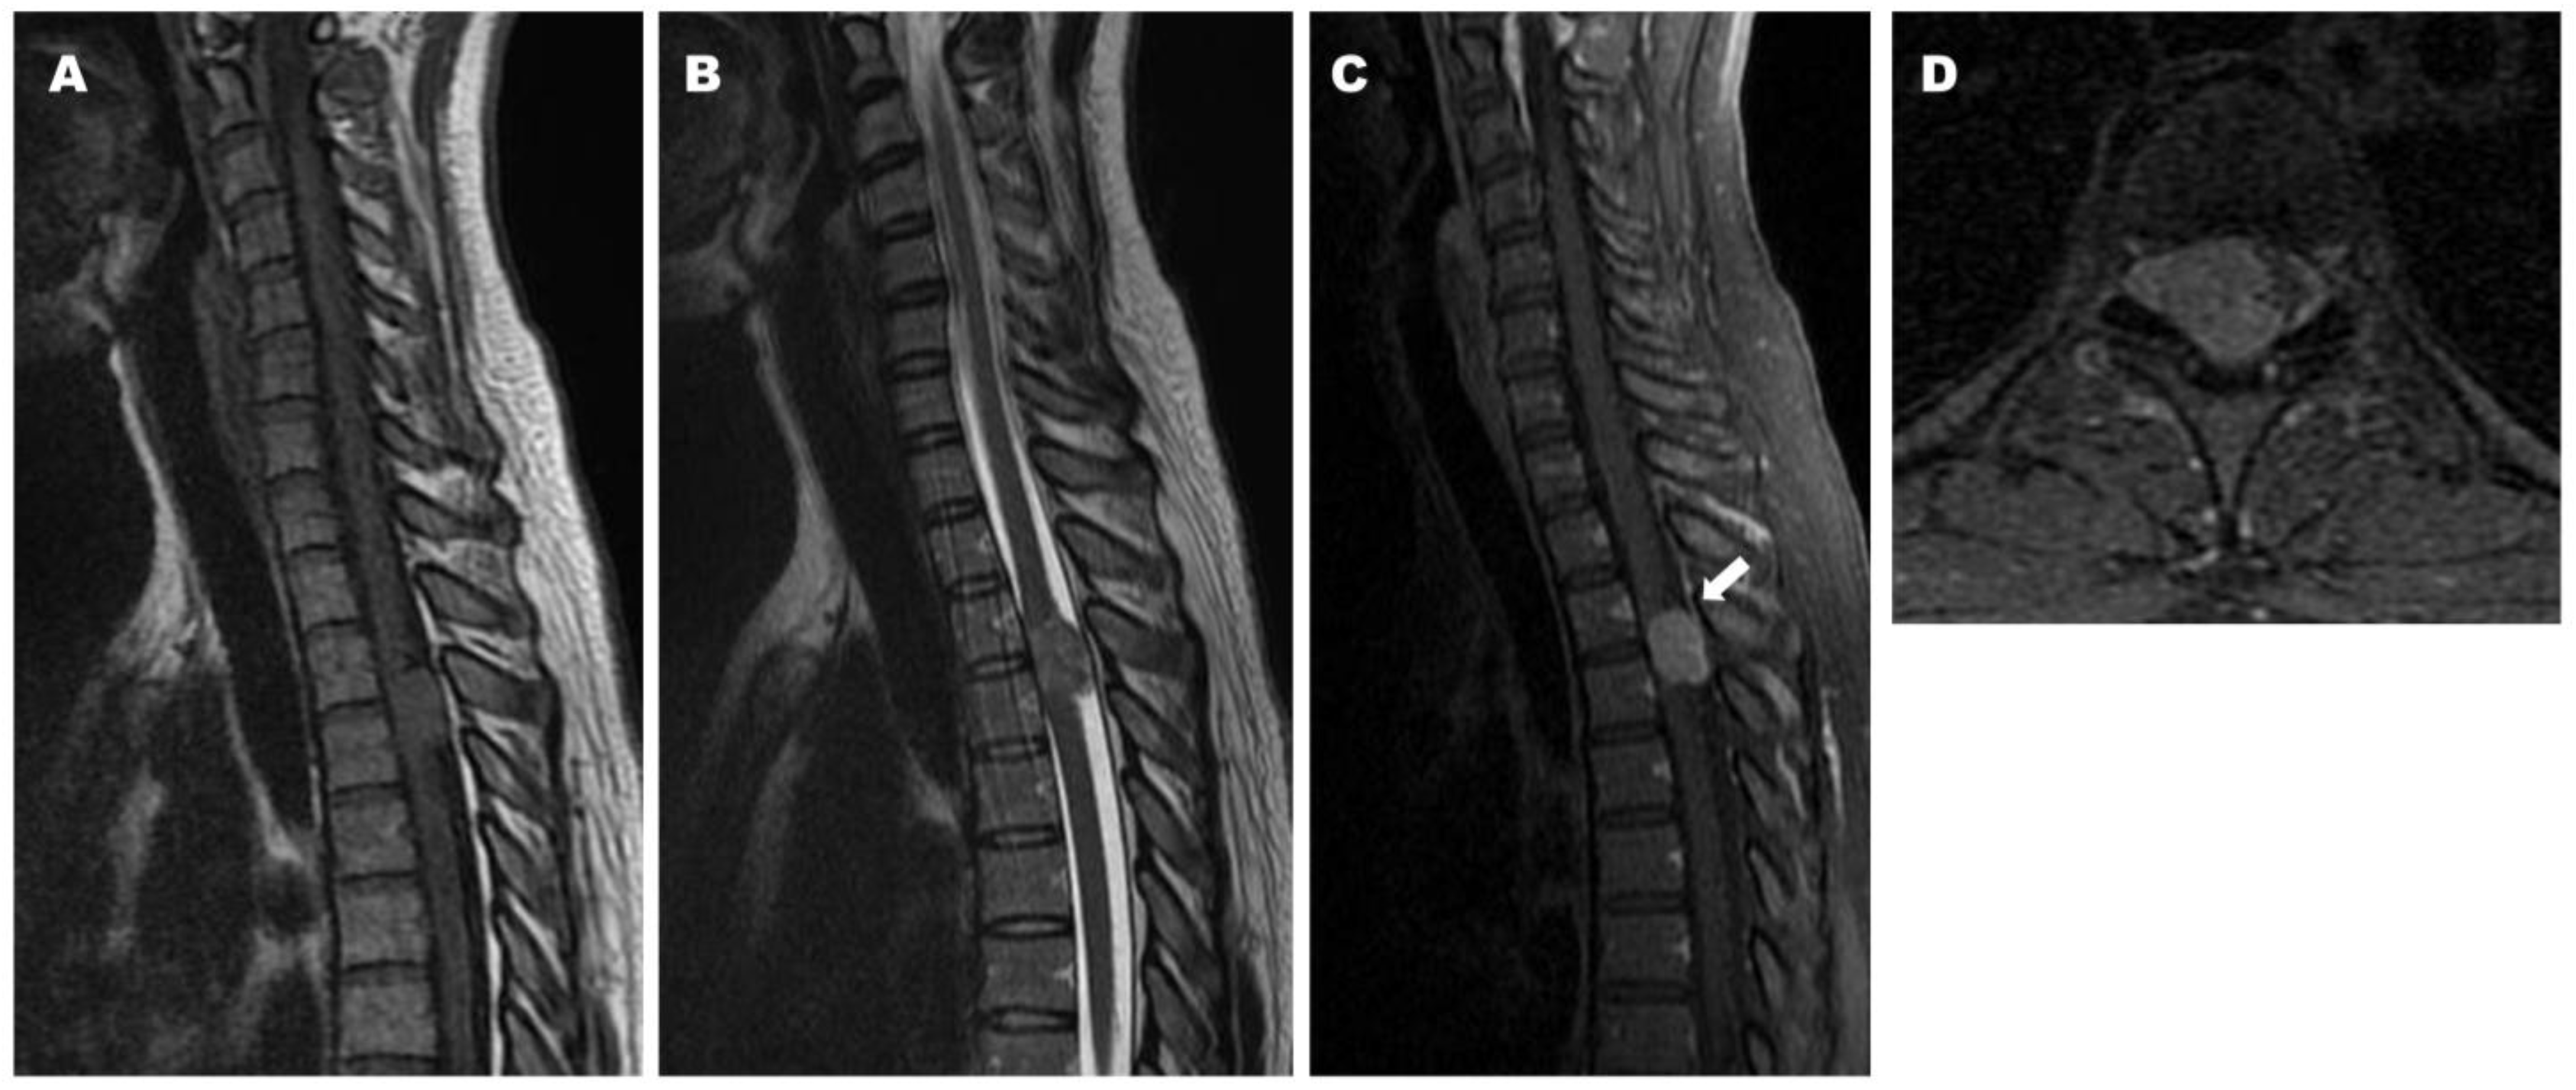

2.2. Case 2